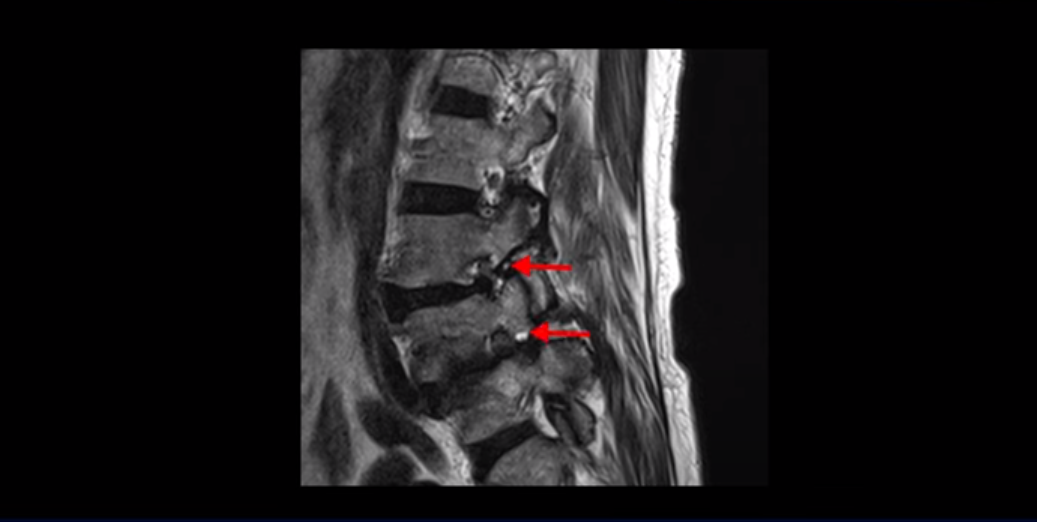

제가 이분 MRI 보면서 설명 드린 후 어떻게 대학병원에서 나사 6개 박는 수술밖에 방법이 없다고 들은 전방전위와 협착증 환자가 비수술 근육재활치료로 좋아질 수 있는지, 치료는 어떻게 하는 건지 자세히 설명 드리도록 하겠습니다.

MRI를 보면 보시다시피 전방전위가 2마디가 있는데, 4번 5번 마디는 2단계로 매우 심합니다.

이렇게 전방전위가 있으면 신경 구멍을 좁히게 되니까 협착이 다른 사람에 비해 더 쉽게 올 수 있습니다. 그래서 오른쪽 신경 구멍을 보면 3번 4번, 4번 5번 추간공이 많이 좁아져 있습니다.

왼쪽 신경 구멍도 두 마디가 좁아져 있어서

이분은 오른쪽, 왼쪽 양쪽 엉덩이와 다리가 다 저리고 아파 못 걷습니다. 이렇게 전방전위와 협착도 심하니까 국내 최상급 대학병원에서도 나사 6개 박는 유합술을 반드시 해야 한다는데, 어떻게 이런 상태가 수술 없이 치료가 가능할까요? 지금부터 설명 드립니다.